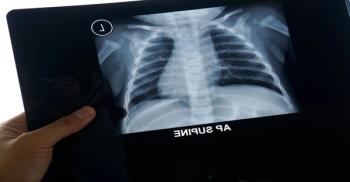

Radiologists in the United Kingdom are now using radiography to speed up COVID-19 identification.

ACR recommends against using CT as a first-line test; offers advice on imaging use.

Chest CTs and X-rays highlight characteristics of EVALI in teens.

Patients with the coronavirus who develop pneumonia exhibit similar findings on chest CT scans.